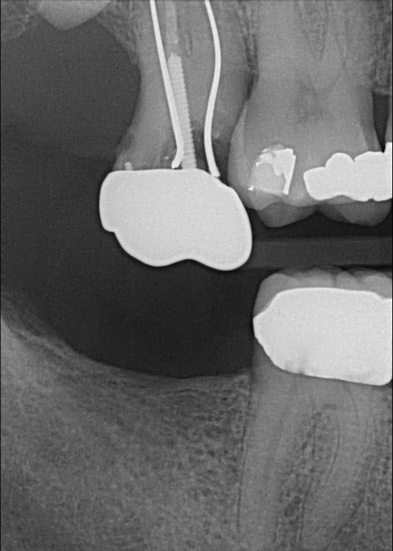

Fig 3. Patient No. 1, contralateral side; in 2009 patient presented with teeth Nos. 15 and 18. Subsequently, tooth No. 18 was extracted due to tooth fracture.

Figure 3

Fig 4. Patient No. 1 in 2016, with extrusion of tooth No. 15. Two different experiences in the same mouth, as shown in Figs 1–2 and Figs 3–4, underscore the unpredictability of extrusion.

Figure 4

Another consideration is mean vertical displacement of unhampered posterior teeth, which in some studies was minimal: 0.8 mm37 and 0.9 mm30 (Table 1). Yet, there could have been sites where the amount of extrusion was clinically relevant. When Lindskog-Stokland et al assessed the risk of over-eruption using 1 mm as a threshold, they stated there was an odds ratio of 3.3 that unimpeded molars would extrude 1 mm compared to opposed molars.30 Based on their calculations, however, it is unclear which patients with a missing molar are at risk of over-eruption (Figure 1 through Figure 4). Indeed, if susceptible individuals could be identified, then restorative therapy could be initiated to stabilize their occlusion (eg, tooth replacement). Furthermore, odds ratios can be highly misleading, and predictive values would provide clinicians a better perspective as to what percentage of sites may experience significant extrusion.41,42